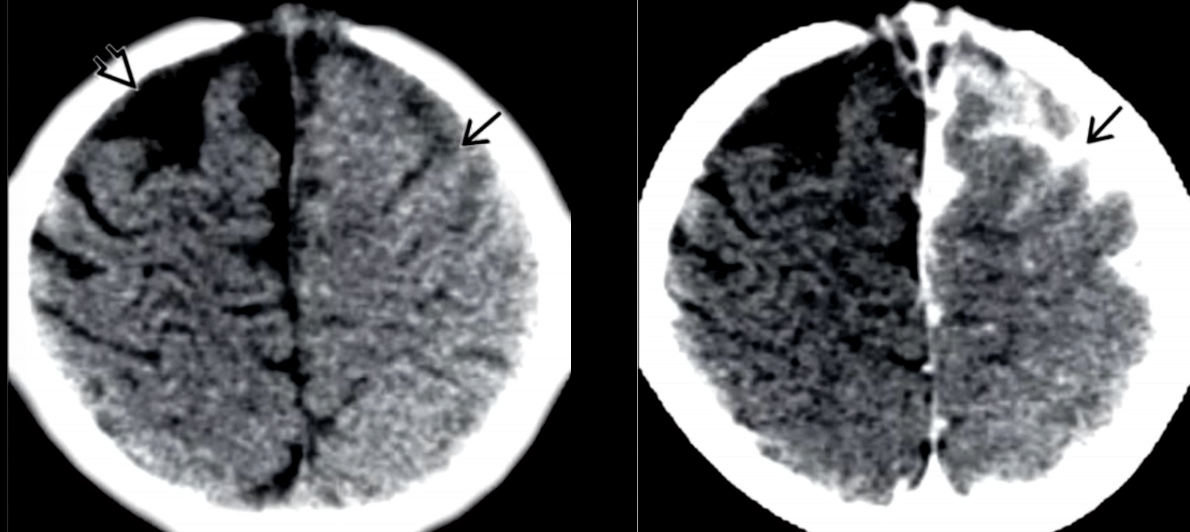

¿PARA QUE CARAJOS SE HACE ENTONCES LA IMAGEN EN MENINGITIS?

Descartar complicaciones

Complicaciones

Hidrocefalia

Abscesos

Cerebritis

Ventriculitis

TC

Borramiento surcos

HD surcos y cisternas

Contraste: hipercaptación giral